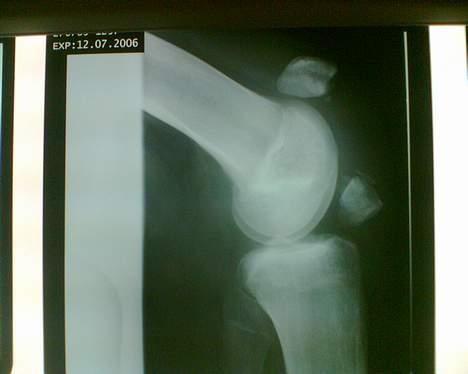

Aprilia Sonic GP ( SOLGT )  - Min knæskald efter uheld den 21 april, har gået med det i ca 3 måneder :/ og er blevet operert D.13 Juli billede 5

Aprilia Sonic GP ( SOLGT )  - De har samlet min knæskald som var i 2 stykker, og har ikke brugt tråd til at samle det med , men klips :/  billede 6